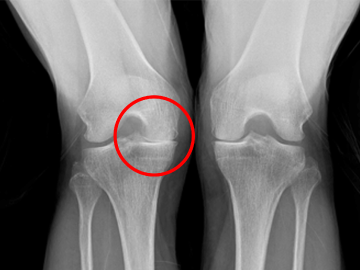

정상

퇴행성관절염

(관절의 간격이 좁아져 맞닿아있음)